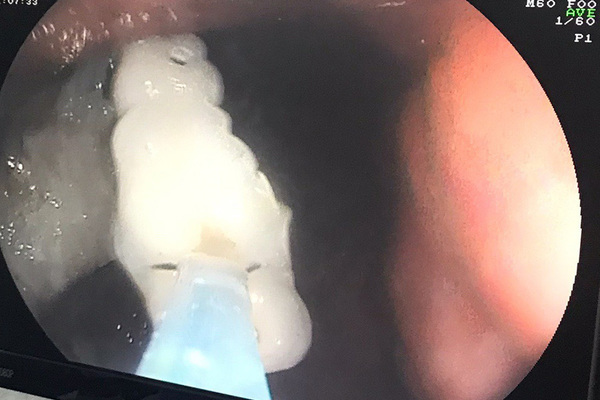

Quả dưa leo kẹt trong trực tràng chàng trai 19 tuổi

Bệnh viện Nguyễn Tri Phương (TP.HCM) đã phẫu thuật để lấy ra dị vật dài hơn 10cm trong vùng hậu môn trực tràng của nam thanh niên.